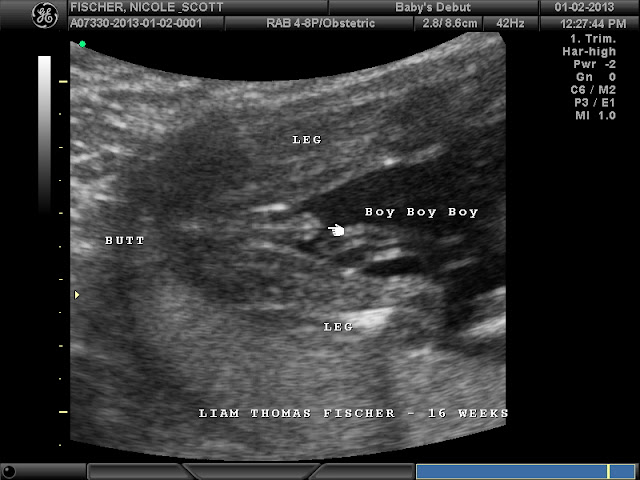

I feel kinda bad posting this wee willy winky online for the world to see, but whatever...Im sure I'll embarrass him in worse ways. :)

Everything looked great, mind you this was not a diagnostic ultrasound, but the tech also works in a hospital, so if she would have seen something she would have referred us to the Dr.

We saw fluid in his stomach and kidneys which means he is drinking the amniotic fluid and digesting it, and we saw the 4 chambers of his heart pumping away. His heartrate was 145 at the ultrasound studio and at the midwives.